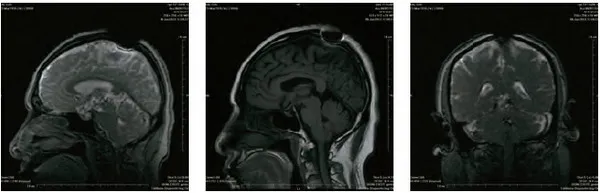

开初仁波且MRI核磁共振脑断层扫描医学图片

这是开初仁波且修金刚换体禅后,在加州医疗中心检查身体时拍摄的MRI核磁共振检测照片。可以清晰看见开顶后,头顶大乐轮门处头骨、皮肉等大开,开口宽约两英寸,脑髓开出鸡蛋大的凹洞。更令人震撼的是,当开初仁波且拍摄扫描照片时,整块头骨突然不见,而呈现出弥勒菩萨乳胎婴童像,身搭俱袍,手脚呈现,心空大洞,跏趺而坐,在电脑上清晰可见五官面容,眼睛、鼻子、嘴巴。